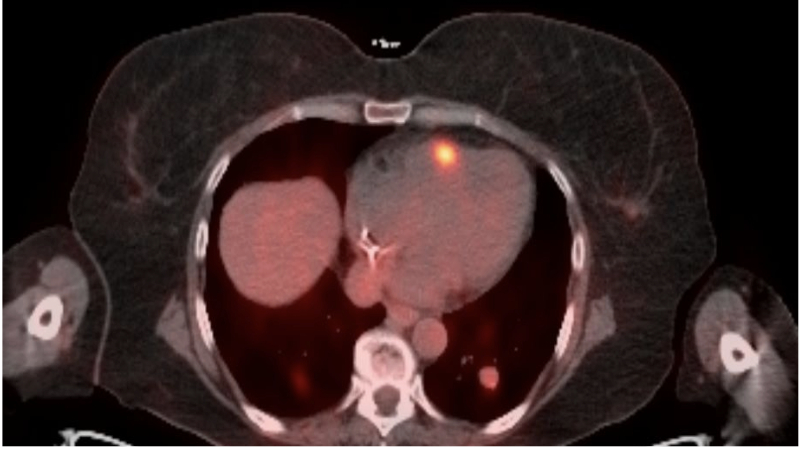

A 59-year-old woman underwent resection of CDK4-positive, BRAF/KIT/NRAS-negative

cutaneous melanoma of the left thigh and foot. Four months later, an 18F-FDG PET-CT (figure 1)

revealed disseminated disease with intense pericardial uptake. Cardiac MRI (figure 2) showed a

3.3 cm right-ventricular (RV) free-wall mass and a 1.1 cm left-ventricular (LV) apical lesion;

transthoracic echocardiography (TTE) (figure 3) confirmed mass location with preserved

biventricular function.